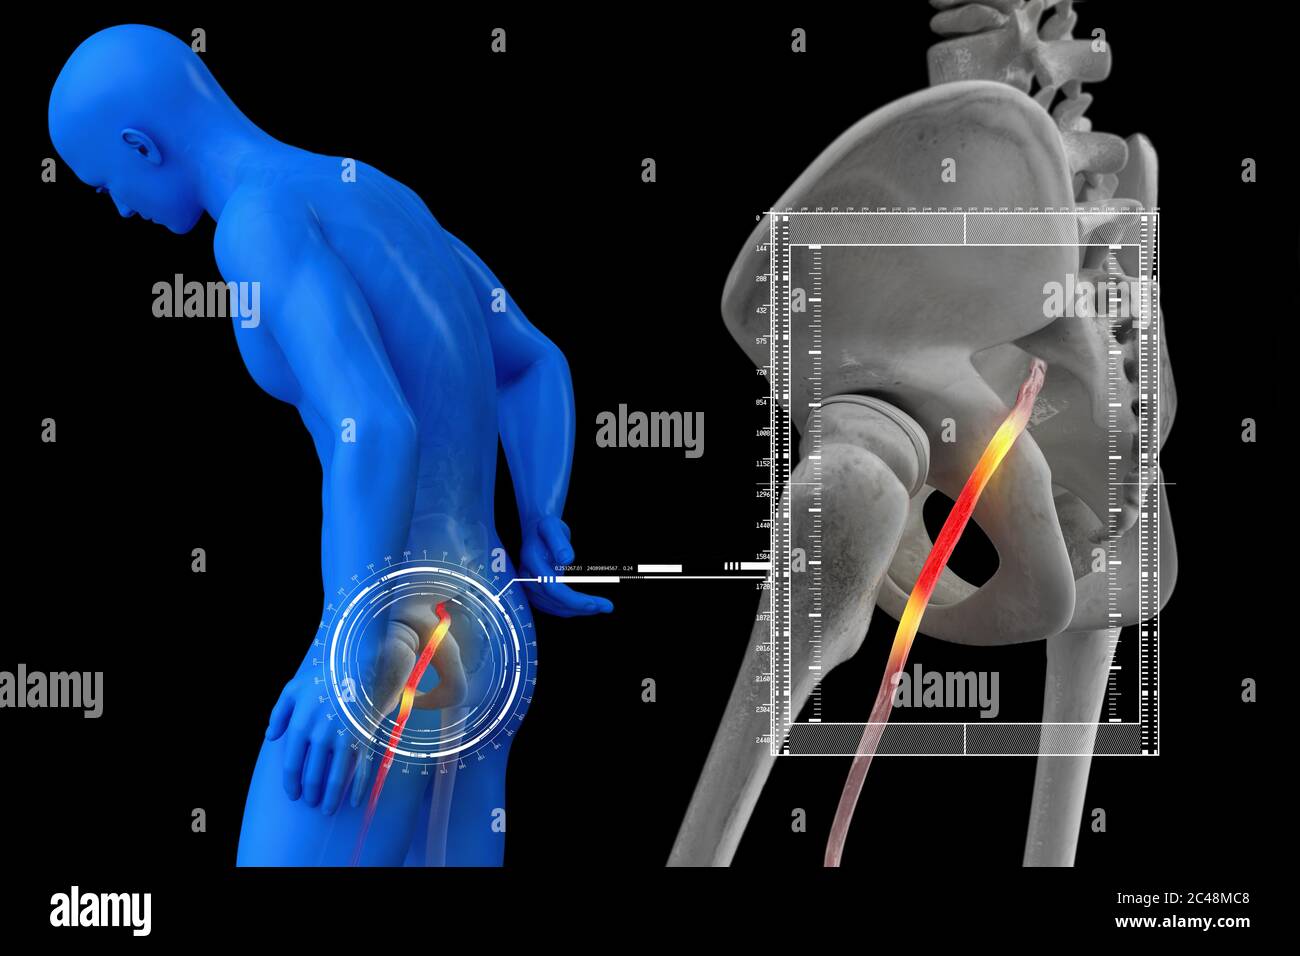

Nerf sciatique humain pincé, vision anatomique. illustration 3d. Banque D'Imageshttps://www.alamyimages.fr/image-license-details/?v=1https://www.alamyimages.fr/nerf-sciatique-humain-pince-vision-anatomique-illustration-3d-image364067992.html

Nerf sciatique humain pincé, vision anatomique. illustration 3d. Banque D'Imageshttps://www.alamyimages.fr/image-license-details/?v=1https://www.alamyimages.fr/nerf-sciatique-humain-pince-vision-anatomique-illustration-3d-image364067992.htmlRF2C48MC8–Nerf sciatique humain pincé, vision anatomique. illustration 3d.